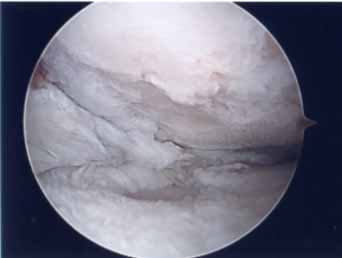

第1段階軟骨形成術

軟骨障害は最初亀裂または剥離で始まります。この状態が第一段階軟骨障害です。このことはあまり一般に知られていません。この最初の亀裂や剥離状態のうちに対処することが最も結果が良好となります。亀裂や剥離が進んでしまうと②の状態になります。

第2段階軟骨形成術

軟骨の剥離や亀裂が①より少し進んだ段階です。放っておくとさらに軟骨欠損が進み軟骨障害は広くなり且つ深くなります。この段階ではまだドリリングなどの操作は不要です。第3段階軟骨障害との間は幅広く関節鏡で見てみないと最終的に判断できません。この段階では手術結果は比較的よく平均75~90点ほどになります。